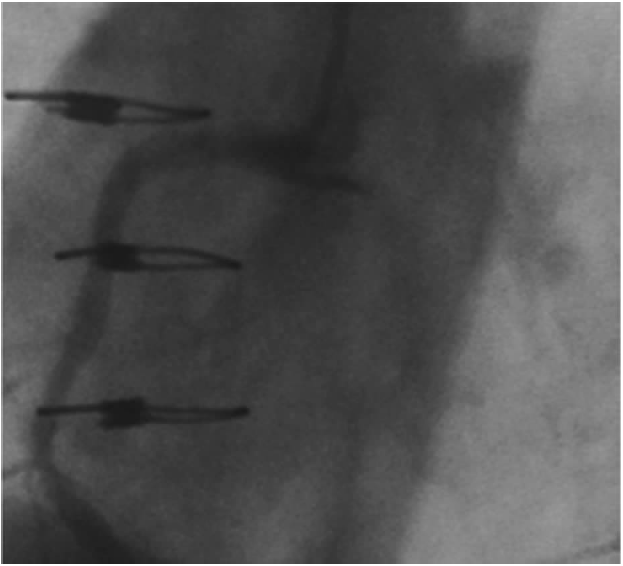

图15.3 在右冠近段球囊扩张后,在主动脉壁上右冠开口处出现持续的造影剂填充。

冠状动脉夹层继发的逆向性主动脉夹层通常在右冠(更常见)近段或前降支(图15.3)球囊扩张时发生。尽管很少见,若在任何开口处或近段病变球囊扩张或支架后出现无法解释的胸痛、低血压,或在主动脉根部持续造影剂填充,均应充分排除。如果及早发现,需立即采取补救措施,包括对开口处病变置入支架,以封闭夹层。当出现严重主动脉瓣膜反流、主动脉上血管受累及夹层延展时,应请外科会诊。如以上情况均未出现,应仔细观察。随访胸部CT能够鉴别无需进一步治疗的稳定患者与出现并发症需手术的患者。